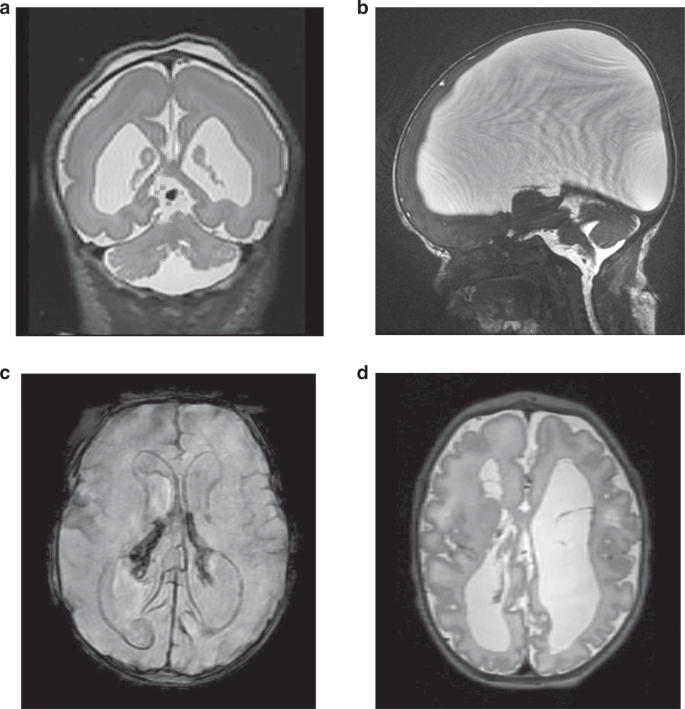

Brain MRI is a superior neuroimaging modality following the prenatal identification of a brain malformation, disruptive brain injury, or both.53 Postnatal MRI is important for the detection of late-emerging imaging findings, such as malformations of cortical development, which can occur on a primary basis, or secondary to disruptive consequences of brain injury early in brain development, for example, those due to congenital infection, hypoxia-ischemia, and hemorrhage.21,34,53,54 Imaging at term-equivalent age is also necessary to examine the severity of malformations of hindbrain development given that the cerebellum undergoes a rapid period of volumetric growth, surface area expansion, and increased complexity during the third trimester. The full extent of brain malformations can be missed on fetal brain MRI, particularly when performed in the late second trimester and early third trimester; understanding the constellation of malformations informs both the etiologic examination, as well as prognosis.54 Some patterns of postnatal MRI findings can point toward specific etiologies (Table 2, Fig. 2). Susceptibility-weighted sequences (e.g., susceptibility-weighted imaging [SWI], or gradient echo imaging, [GRE]) to identify hemosiderin/remote hemorrhage should be obtained, and specifically requested if not routinely included. In selected cases, additional sequences may be helpful, including: (a) magnetic resonance arteriography and venography in cases of suspected vascular malformation or parenchymal hemorrhage,19 (b) diffusion tensor imaging in dysgenesis of the corpus callosum to assess the extent of callosal development and to exclude subtler variants of holoprosencephaly,22 and (c) magnetic resonance spectroscopy (MRS), which can support a diagnosis of inborn errors of metabolism such as mitochondrial disorders with the presence of a lactate peak, non-ketotic hyperglycinemia (NKH) with evidence of an abnormal glycine peak, and peroxisomal disorders with an abnormal double lipid peak.55 Imaging acquisition parameters should be protocolized to optimize visualization of the developing brain, and interpreted by neuroradiologists with expertise in the neonatal brain. There is broad consensus to obtain neonatal brain MRI without sedation or anesthesia unless clinically necessary for another indication (i.e., protecting a critical airway).

a Coronal T2-weighted MRI in newborn with TUBA1A variant showing pachygyria-lissencephaly spectrum, ventriculomegaly, and cerebellar hypoplasia. Prenatal presentation in this case with ventriculomegaly on 38-week ultrasound for growth. b Sagittal T2-weighted MRI in newborn with L1CAM variant showing very severe ventriculomegaly due to aqueductal stenosis. Initial prenatal presentation with mild ventriculomegaly on anatomy ultrasound at 21 gestational weeks and progressive ventriculomegaly on ultrasound throughout pregnancy. c Susceptibility-weighted MRI in newborn with COL4A1 variant and prenatal diagnosis of intraventricular hemorrhage and right posterior periventricular hemorrhagic infarction with ventriculomegaly. Initial diagnosis on fetal brain MRI obtained at 37 gestational weeks for ventriculomegaly on follow up growth ultrasound at 35 gestational weeks. d Axial T2-weighted MRI in newborn with PDHA1-related pyruvate dehydrogenase complex deficiency showing agenesis of the corpus callosum, ventriculomegaly, cystic cavitation of the white matter, and diffusely abnormal sulcation. Prenatal presentation with similar findings on ultrasound and fetal brain MRI at 32 gestational weeks.